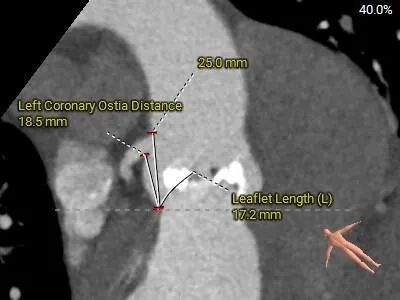

术前CT评估

Type0型二叶式主动脉瓣,LVOT偏敞口型,非横位心。

重度钙化,HU 850积分1711mm3。

左冠18.8,右冠19,综合分析冠脉阻挡风险适中。

瓣上多平面分析。

•Type0型二叶瓣,左右冠脉异窦,瓣叶增厚伴重度钙化,钙化团块主要沿双侧瓣叶分布,无窦下部分钙化延伸至LVOT,预估假体瓣膜植入锚定难度适中,受钙化块挤压,存在瓣膜移位及瓣周漏可能,同时需防范根部撕裂风险,

•左、右冠高度可,切线位测量,无冗长瓣叶,结合瓦氏窦、STJ内径综合预估,冠脉阻塞风险适中,